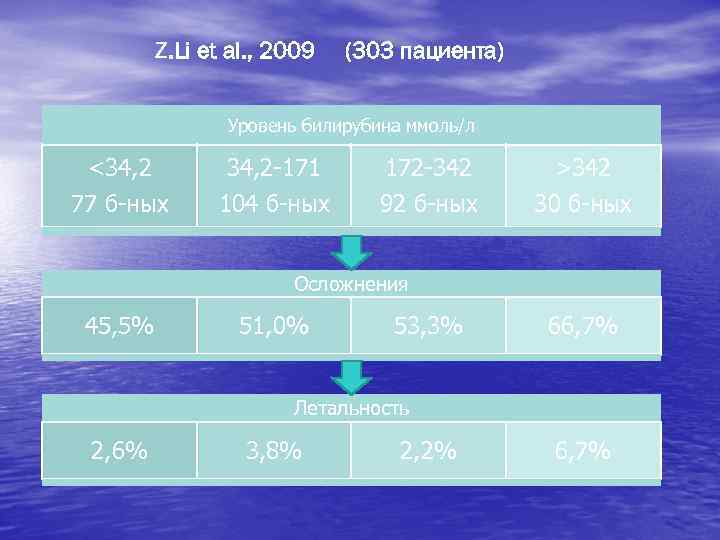

Z. Li et al. , 2009 (303 пациента) Уровень билирубина ммоль/л <34, 2 77 б-ных 34, 2 -171 104 б-ных 172 -342 92 б-ных >342 30 б-ных Осложнения 45, 5% 51, 0% 53, 3% 66, 7% Летальность 2, 6% 3, 8% 2, 2% 6, 7%